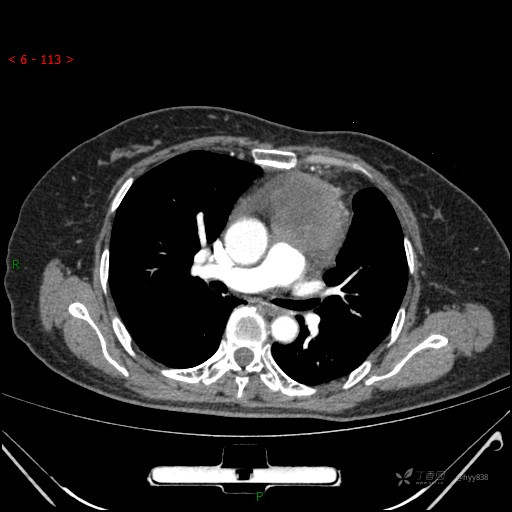

简要病史:患者诉3月余前患新冠肺炎,出现持续性胸闷,活动后可缓解,无胸前区压榨感,无畏寒发热不适,无胸痛咯血、呼吸困难,无恶心、呕吐,无腹痛、腹胀、腹泻等不适,未予以重视,未行特殊处理。患者胸闷持续存在,为进一步诊治,3天前于本院查胸部CT提示前纵膈团块状软组织密度影,肿瘤性病变可能,心包积液,左上肺磨玻璃结节,右下肺增殖灶可能建议进一步检查。门诊以“前纵膈占位” 收入我科。 患者本次起病来精神、食欲、睡眠尚可,大小便正常,体力、体重无明显变化。

辅助检查:CT

胸部CT平扫

动脉期